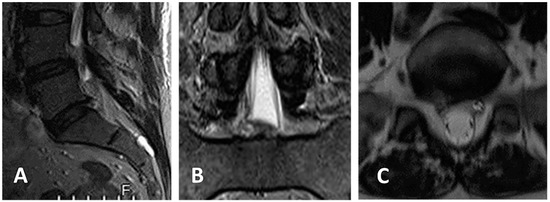

3.3. Clinical Case 1